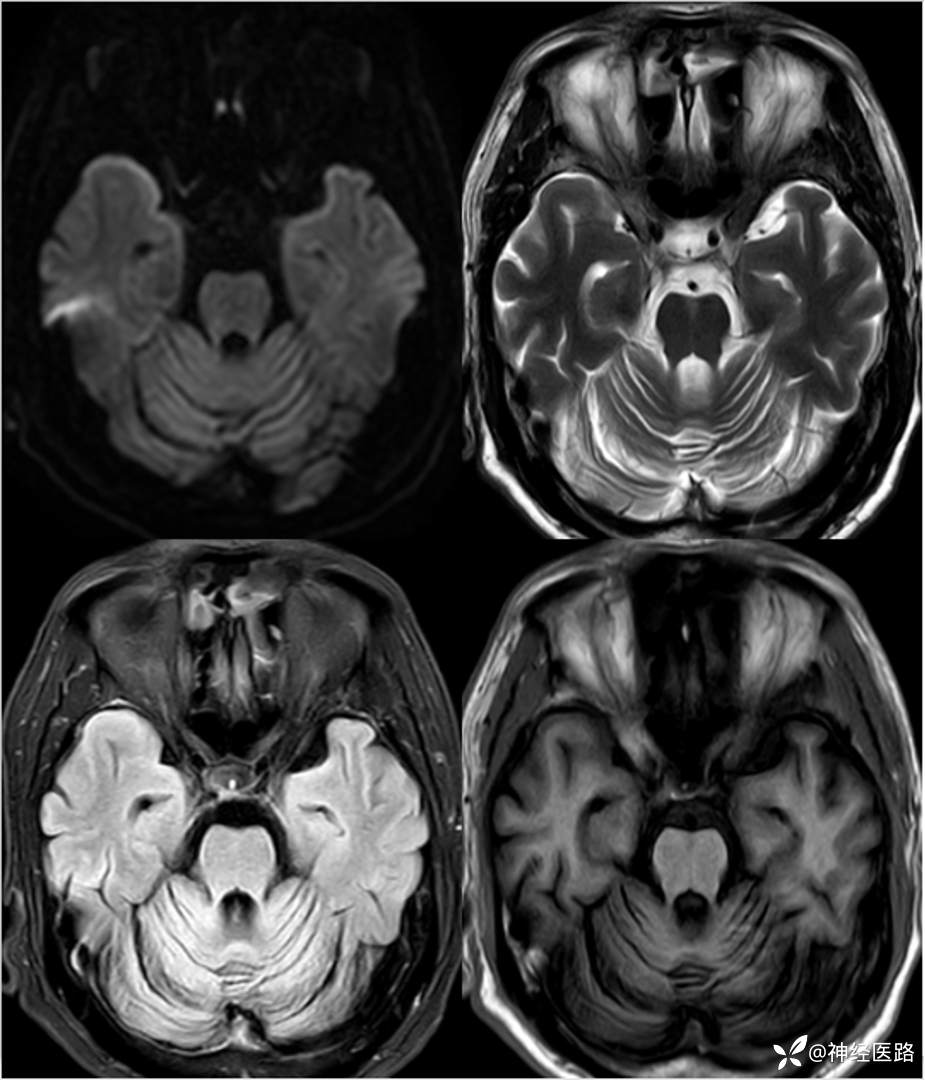

辅助检查:头部磁共振:1.颅脑DWI未见明显异常扩散受限。 2.脑白质高信号,脑萎缩。3.双侧上颌窦、双侧筛窦、双侧额窦炎。

两次影像对比